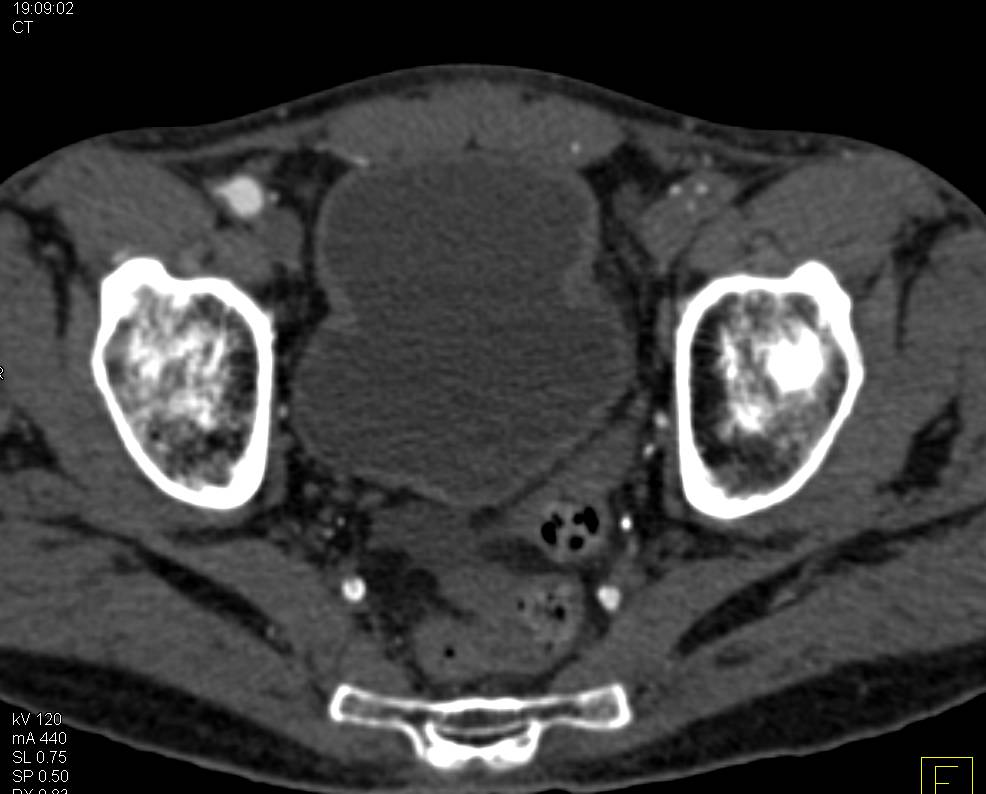

Beautiful 3D VRTs of Coronary Artery Bypass Graft (CABG) with Venous and Left Internal Mammary Artery (LIMA) Grafts